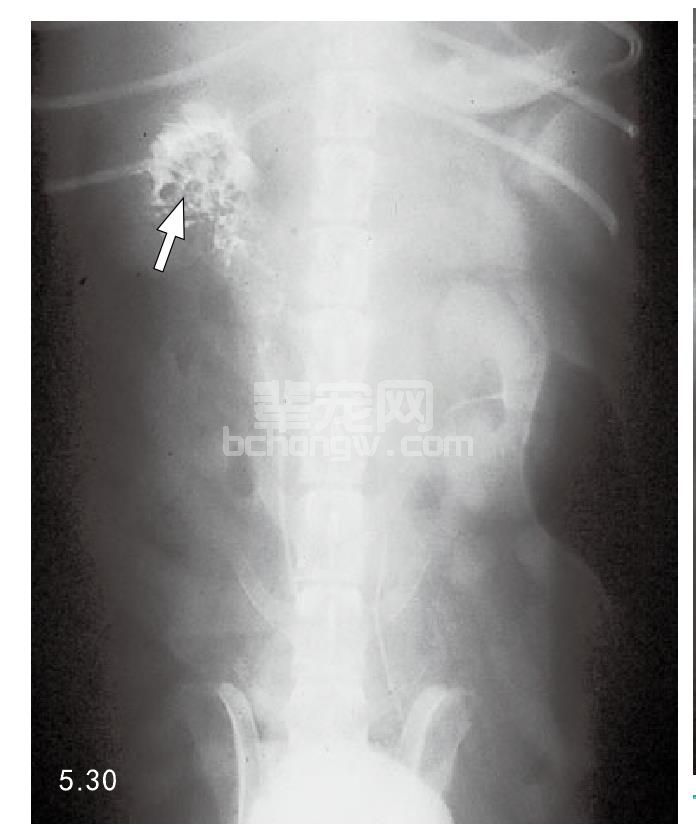

诊断 犬的肾脏肿瘤,腹部X线片显示有不规则增大的肾脏并能看到矿化区域。肾X线尿路造影见图5.29。 显示肾脏感染部位异常血管灌注,肾盂造影图像可以显示收集系统的变形(图5.30)。超声波可以检测恶化组织 的异常回声(图5.31)。肾脏团块的直径大于5cm很可能是肾脏肿瘤。血尿持续存在,可利用膀胱镜检查病变的 肾脏输尿管以显示出血部位(图5.32)。尿液细胞学评价并不可靠,只有切除的肾脏活组织检查才能确诊。犬和 猫的淋巴瘤、针管抽吸或活组织检查可确诊。放射学检查可确定是否转移。

图5.30 犬肾脏肿瘤时造影显示:收集系统异常的肾盂背腹位变形(箭头所指)。